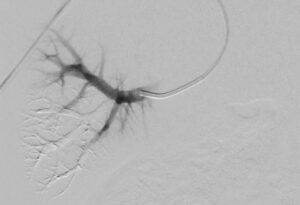

“We are impressed with the GPX embolic,” said Andrew Holden, M.D., MBChB, FRANZCR, EBIR, ONZM, Director of Interventional Radiology, Auckland City Hospital, Auckland, New Zealand. “We delivered GPX through a long 150cm 2.4F microcatheter from the patient’s radial artery. GPX was easy to use, precise, and occluded the tumor well. We look forward to using GPX across a broad range of applications to improve patient care.”

“GPX is easy to prepare, deliver, and control,” said Ryan O’Hara, M.D., Interventional Oncologist, University of Utah, Salt Lake City, Utah USA. “GPX is responsive to the physician and layers well in the vessel during delivery resulting in improved targeting and control. I see potential for this embolic in interventional oncology and other peripheral vascular and neurovascular uses.”